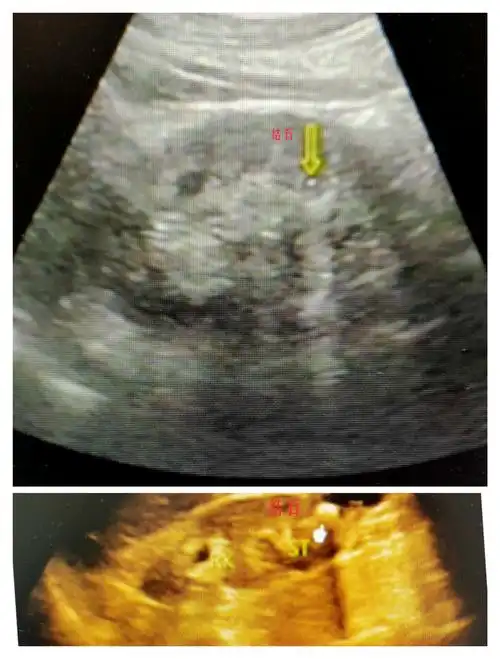

青海省康乐医院超声科邀您一起了解:超声下的肾结石.

【秀医超声小课堂】——肾脏内的强回声不一定是结石